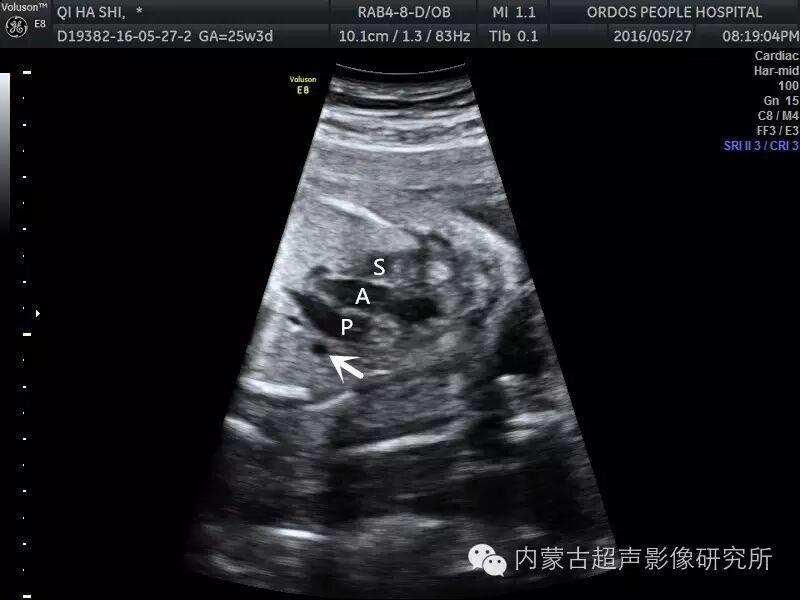

病例报告:超声诊断胎儿永存左上腔静脉一例

永存左上腔静脉

四维结果显示永存左上腔静脉